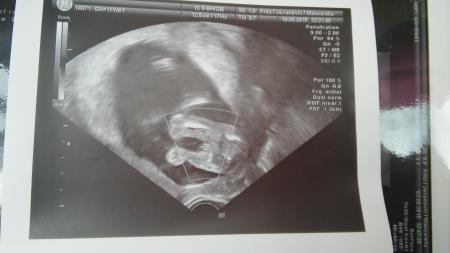

Das ist das potenzielle Outingbildchen von heute :-)

Hallo ihr Lieben :-) war heute beim Frauenarzt und wieder gab es kein eindeutiges Outing. Wir sahen im Ultraschall ein Bild wo es uns eig direkt klar war, Junge!!! Der Arzt sagte noch wir gucken noch schnell wo die Nabelschnur liegt und machte den Doppler an. Und wo verlief sie? Genau über dem potenziellen Penis er sagt für ihn sieht es trotzdem sehr nach Junge aus und er wundert sich sehr, dass die andere Ärztin ein Mädchen erkannt haben will. Ich bin einfach so gespannt, wir wünschen uns einfach ein gesundes Kind und haben schon Junge und Mädchen zuhause, also es ist uns total egal. Dieses Kind macht es einfach super spannend. Ich hab 2 Bilder angehangen, einmal von heute und einmal von meinem Sohn damals. Für mich sieht es jetzt wieder eindeutig nach Junge aus. Habt ihr Lust mit mir zu rätseln? :-) Nur aus Spass :-) dass es erst nach der Geburt sicher ist, weiss ich ja auch :-)

Unseres ist minimal kleiner und er meinte 70% Junge. Jetzt hat aber in Facebook jemand ein Bild gepostet wo genauso aussieht und ihr wurde Mädchen gesagt. Mir ist es auch egal was es wird, aber man will es halt schon gerne wissen. Hoffe man sieht es in 2 Wochen bei der Feindiagnostik zu 100%

Ja genau, an dem re. Oberschenkel verläuft die Nabelschnur mit her. Erst sahen wir dieses Bild und die Ärztin sagte direkt, eindeutig Junge. Dann machte sie den Doppler an um noch zur Vorsicht nach der Nabelschnur zu gucken und sie verlief genau daher, deshalb sagte sie jetzt ist es wieder unklar :-D das Lustige ist, ich hab die ganze Zeit ein Mädchengefühl. Wo mir dann das erste mal gesagt wurde es ist ein Junge, hab ich mich komisch gefühlt. Keine ahnung wieso. Ich freue mich über beides, nur hat mein Gefühl überhaupt nicht dazu gepasst. Aber ich dachte wie bekloppt, ist ja nur ein Gefühl. Ich hab dann nicht mehr dran gedacht und das Kleine dann auch immer mit " seinem " Namen angesprochen. Als mir die Ärztin im Krankenhaus dann sagte es ist eher ein Mädchen, war plötzlich alles so klar für mich. Gefreut hab ich mich genauso, nur ich wusste plötzlich wieso ich die ganze Zeit dieses komische Gefühl hatte. Und jetzt wird mir wieder gesagt es ist ein Junge und es sieht ja auch stark danach aus, wenn da nicht die Nabelschnur mit liegen würde. Und seit dem ist mein Gefühl wieder so, als stimmt das einfach nicht :-D total komisch kann ich mir nicht erklären. Ich dachte erst vielleicht hab ich eher einen Mädchenwunsch und es ist dann eher Wunschdenken, aber ich hab ja schon Junge und Mädchen hier und beides ist so toll, auch Namen haben wir schon für Beides. Echt komisch. Ich werde wohl abwarten ob mein Gefühl stimmt oder ich einfach verrückt bin :-D die Hauptsache ist wir bekommen ein gesundes Baby!!!